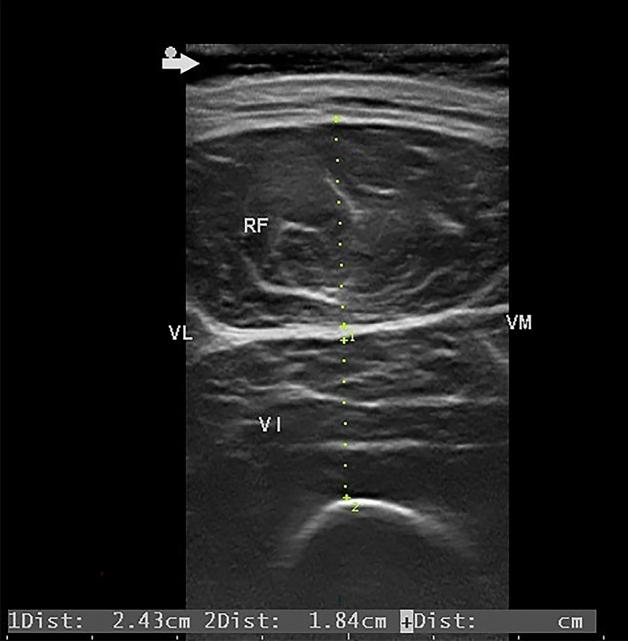

Muscle atrophy greatly affects the prognosis of patients in the intensive care unit, but the rate of change remains unclear. In this prospective observational study, we used ultrasound to measure the change in muscle thickness of the rectus femoris (RF) and vastus intermedius (VI) in 284 patients who were admitted to the SICU of Taoyuan General Hospital between January 1 and June 30, 2020. Patients were excluded if there is a wound at the right thigh which hinders the ultrasonography probe from placing. Daily rates of muscle atrophy were calculated using linear analysis and the ratios of change were plotted against the period of hospitalization. Patient characteristics were adjusted using propensity score matching and differences between men and women were analyzed. A linear mixed model was used to calculate the influence of other factors on muscle loss. The average daily atrophy rates of the RF and VI were 0.84% and 0.98%, respectively. The rate of atrophy was the highest in the third and fourth weeks. Daily atrophy rates of the RF and VI were approximately three times higher in women than in men. Protective factors of muscle atrophy included higher BMI and lower initial thickness of the RF and VI. Our study depicts the trend of muscle atrophy in the ICU and suggests more discussion in prevention to be conducted especially for women.

肌肉萎缩极大地影响了重症监护病房(ICU)患者的预后,但变化的速度尚不清楚。在这项前瞻性观察研究中,我们使用超声测量了 2020 年 1 月 1 日至 6 月 30 日期间入住桃园总医院 SICU 的 284 名患者股直肌(RF)和股中间肌(VI)的肌肉厚度变化。如果右大腿有伤口妨碍超声探头放置,则将排除患者。使用线性分析计算肌肉萎缩的每日发生率,并将变化率与住院时间相对比。使用倾向评分匹配调整患者特征,并分析男女之间的差异。使用线性混合模型计算其他因素对肌肉损失的影响。RF 和 VI 的平均每日萎缩率分别为 0.84%和 0.98%。萎缩率在第三和第四周最高。女性的 RF 和 VI 每日萎缩率大约是男性的三倍。肌肉萎缩的保护因素包括较高的 BMI 和较低的 RF 和 VI 初始厚度。我们的研究描绘了 ICU 中肌肉萎缩的趋势,并建议特别针对女性进行更多的预防讨论。